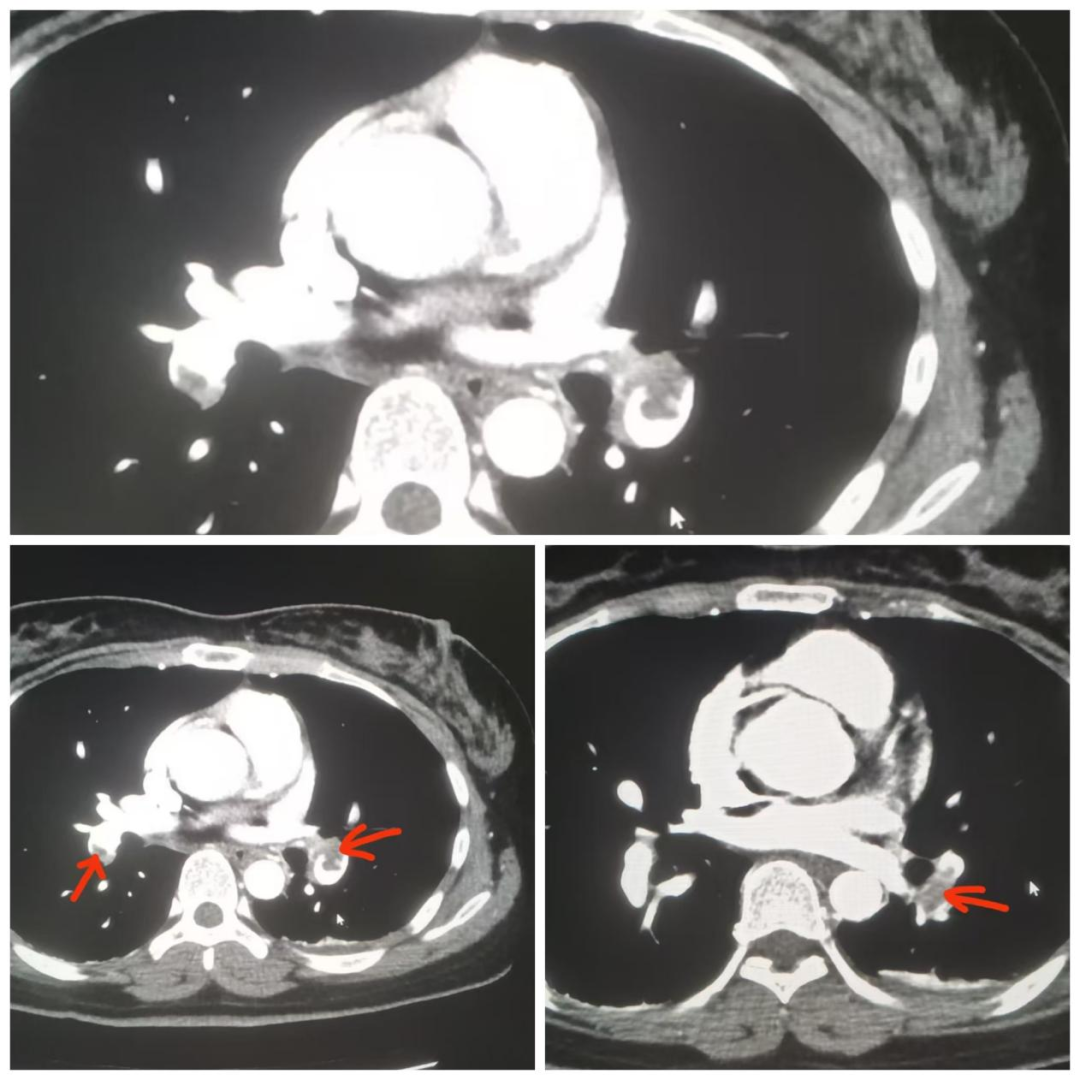

结合患者的病史和超声图像改变,考虑存在肺栓塞的可能性,检查医生立即启动超声科应急预案,护士予以床旁吸氧并电话通知主管医生。后经肺部CTA诊断:两肺下叶肺动脉栓塞。因发现及时,经溶栓等治疗,呼吸道症状明显好转,心率恢复正常,右下肢的肿胀情况也得到缓解。

(肺部CTA:红色箭头所指为肺动脉栓塞位置)